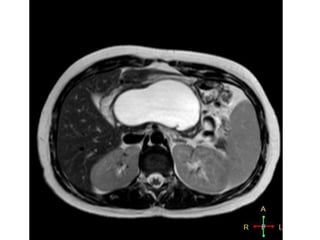

•MRI :- Contrast-enhanced MR is equivalent to CT in the

assessment of pancreatitis.

Radiological Investigations

•MRI –detection of solid component of cyst and in differentiating between

organized necrosis and a pseudocyst